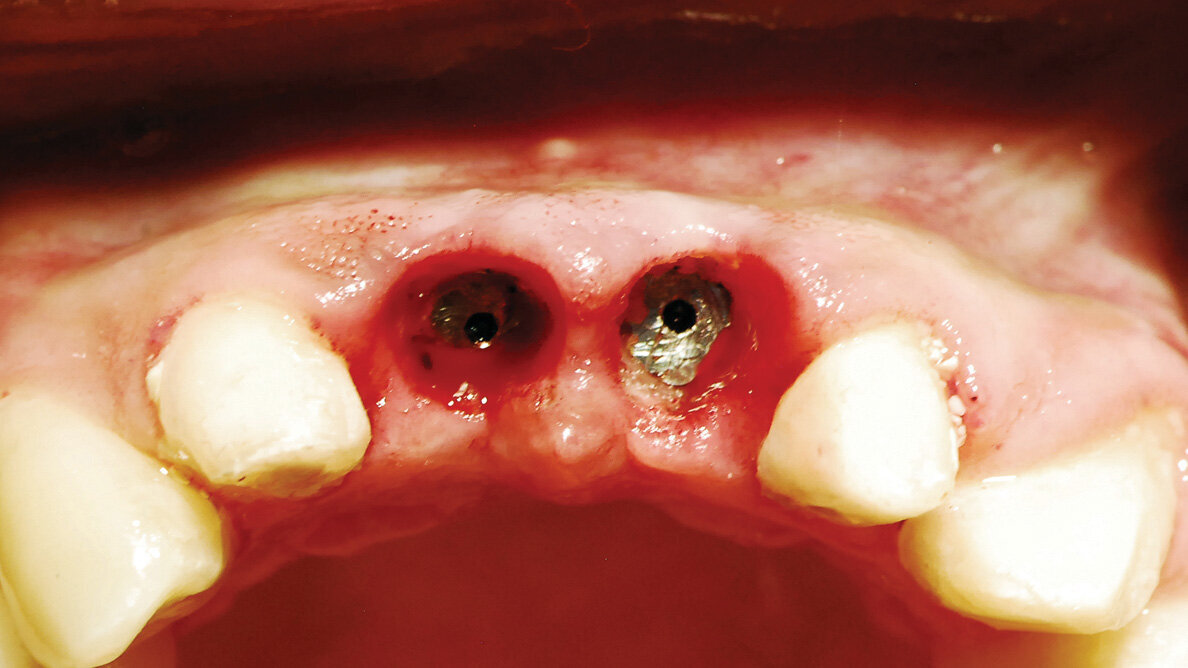

Fig. 11: Removal of the healing abutments at two weeks post-uncovery demonstrates a lack of inflammation of the modified soft tissue. (Photo provided by Dr. Gregori M. Kurtzman)

Two weeks later, the prosthetics returned from the lab (DenMat Labs, Lompoc, Calif.) and the provisional bridge was removed. The healing abutments were removed, and the soft tissue demonstrated a lack of inflammation and a good periodontal health where it had been modified by the diode laser (Fig. 11).